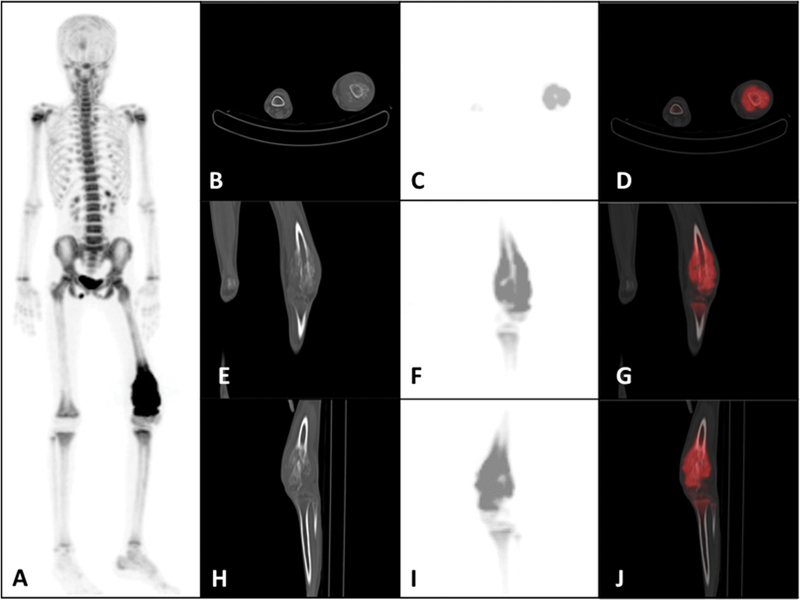

Ewing's sarcoma (ES) is a mesenchymal origin malignant neoplasm that affects children and adolescents. It is the second most common type of bone sarcoma and accounts for approximately 1.5% of all childhood cancers with an annual incidence of 1 to 3 cases per million children under 16 years of age. In this article, we present the case of a 16-year-old adolescent girl. Lung metastasis at the initial diagnosis of ES is relatively uncommon but carries significant prognostic implications. Lung metastases in ES can vary significantly in size, ranging from small nodules (just a few millimeters in size) to the largest reported case being 15 cm. The size of the metastases impacts the choice of therapeutic strategies and the prognosis. Approximately 30% of patients with ES experience a relapse, with the lungs being a common site for metastatic disease. Relapsed lung metastasis on follow-up is a critical concern in the long-term management of ES. We describe a relapsed case of ES in a 16-year-old adolescent girl who presented with a solitary large metastatic right lung mass, with the longest dimension of 16 cm on craniocaudal measurement. The primary site of the tumor was the left distal femur, for which the patient received six cycles of neoadjuvant chemotherapy, followed by en bloc tumor excision and rotationplasty of the left distal femur, after which the patient received seven cycles of adjuvant chemotherapy. Subsequent 5 years of regular follow-up was asymptomatic. Later, the patient presented with back pain and cough, and was diagnosed with a solitary large right lung mass. Computed tomography (CT) guided biopsy of the right lung mass revealed a metastatic ES, for which she underwent chemoradiotherapy. This case highlights the large size of solitary lung metastases in relapsed ES.